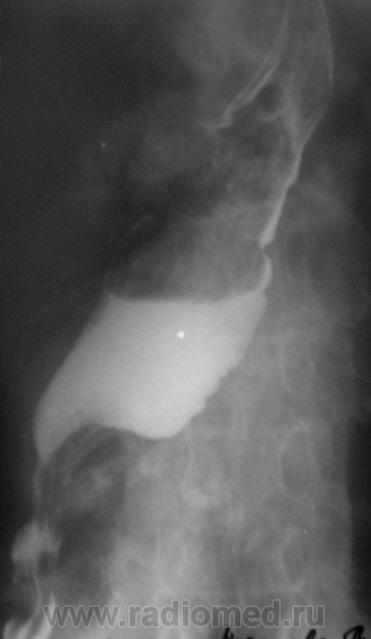

Валентин Львович, а при рентгеноскопии Вы не видели колебания дистального отдела пищевода от передаточной пульсации?

tatyana wrote:

Конечно, видел. Сердце-то огромное. Вот томограммы, которые остались в "заначке".

Томограмма.